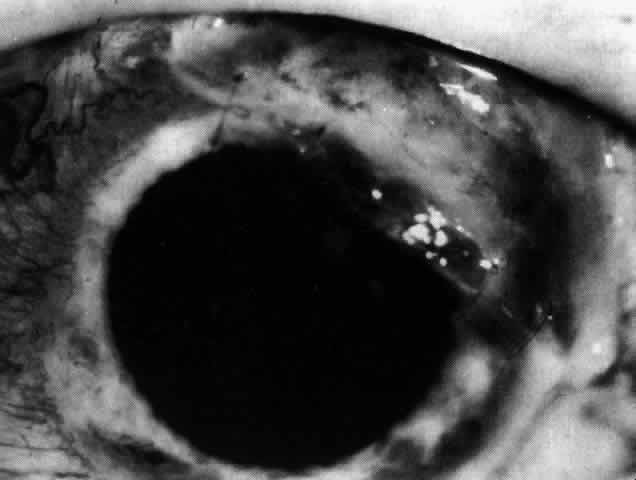

can be mistaken for malignant melanoma.  Fig. 19. Anterior necrotizing scleritis. The eye was removed because of loss of

vision and intractable pain. No form of steroid was given to this patient

because of a severe Pseudomonas infection of the chest. (Courtesy of Professor N. Ashton) Fig. 19. Anterior necrotizing scleritis. The eye was removed because of loss of

vision and intractable pain. No form of steroid was given to this patient

because of a severe Pseudomonas infection of the chest. (Courtesy of Professor N. Ashton)